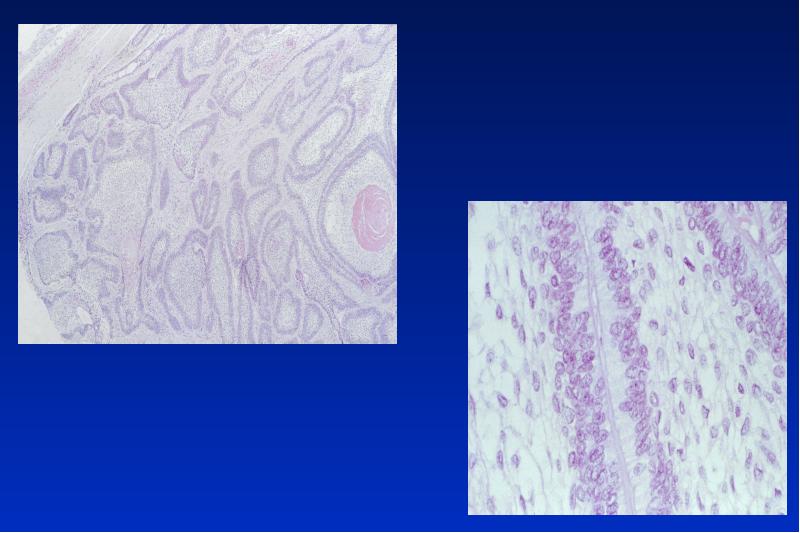

- 21. Odontogene Keratozyste Lok: UK Alter: 20 - 30, 50 - 60

- 45. Unizystisches Ameloblastom 20- 30 Lj unilokuläre Osteolyse 2 histologische